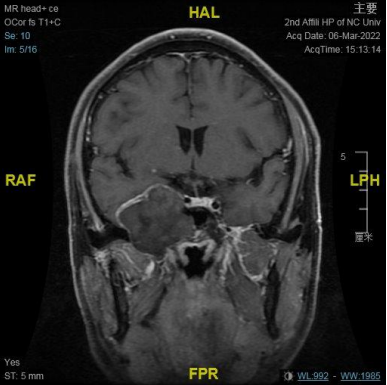

右侧中颅窝鞍旁见一大小约 34 mm✕40 mm✕47 mm 肿块,信号混杂,T1、T2 均呈等低高混杂信号,DWI 呈不均匀混杂信号,边缘包膜呈稍长 T1 短 T2 信号,肿块边界清;肿块无强化,边缘包膜呈明显强化。

结合此病例影像学特点:T1、T2 均呈等低高混杂信号,肿块边界清;肿块无强化,边缘包膜呈明显强化。

从 MRI 增强扫描上肿块无强化,可与神经鞘膜瘤相鉴别;CTA 成像无强化环及强化结节表现,肿块将颈内动脉向后推挤,MRI 增强也无病变周边高信号环及典型的动脉搏动伪影表现,这些影像学表现上可与动脉瘤相鉴别。